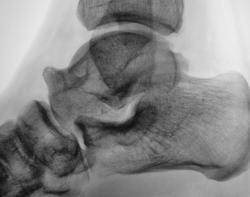

Пол пациента: Мужской пол Тип патологии: Другое Область исследования: Скелетно-мышечная система Методы исследования: Rg Пациент направлен врачом хирургом в рентгеновский кабинет по поводу болей в голеностопном суставе. Произведена рентгенография голеностопного сустава Ваше мнение уважаемые коллеги? Tue, 06/10/2009 - 22:21 #1 Ермолаев Offline Last seen: 8 years 11 months ago Joined: 07.02.2009 - 16:33 Posts: 670 Думаю, что имеет место артроз голеностопного сустава и таранно-ладьевидного, таранно-пяточного суставов. Только это следствие, а причина мне видится в наличии повреждения дистального межберцового синдесмоза. dok Tue, 06/10/2009 - 22:48 #2 В.Б. Серов Offline Last seen: 1 month 2 weeks ago Joined: 16.07.2008 - 10:15 Posts: 1361 Дугообразная деформация костей, с линейными зонами перестройки, плоскостопие. Полный комплект дефектов Зри в корень!

Думаю, что имеет место артроз голеностопного сустава и таранно-ладьевидного, таранно-пяточного суставов. Только это следствие, а причина мне видится в наличии повреждения дистального межберцового синдесмоза.

Дугообразная деформация костей, с линейными зонами перестройки, плоскостопие. Полный комплект дефектов